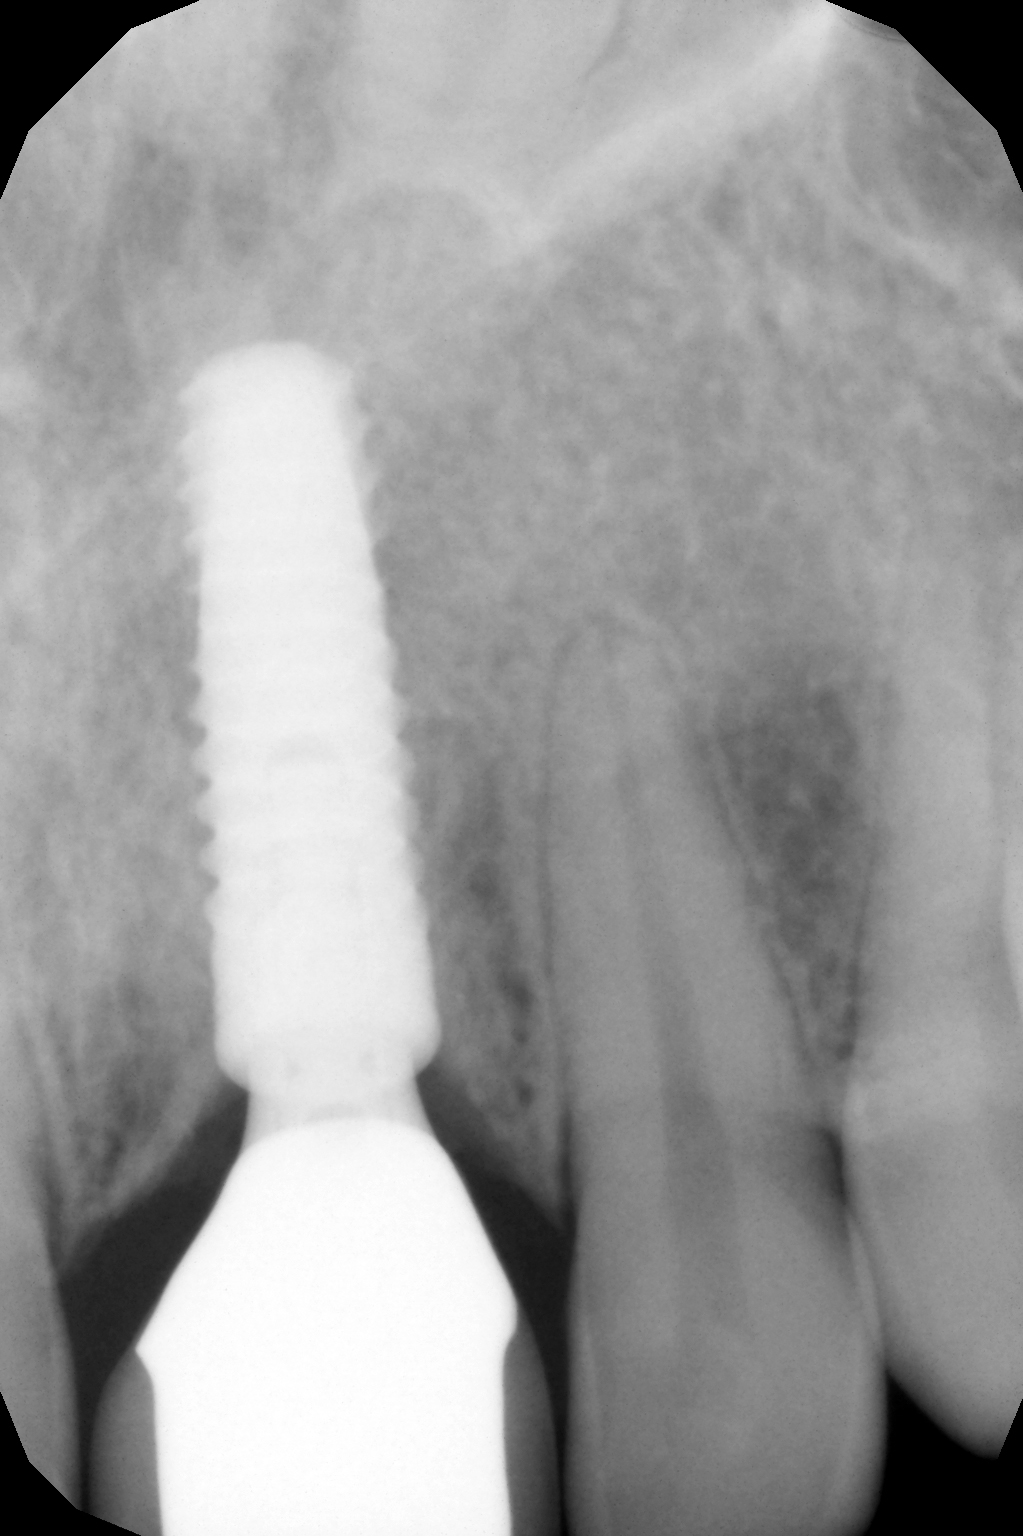

The mucoperiosteal flap was lifted palatally and partially mobilized vestibularly. A 14 mm long BioniQ implant from LASAK with Ø 4 mm was inserted and a temporary abutment was attached after removing the implant carrier.

The X-ray after three years also shows a healed socket without resorptive changes.